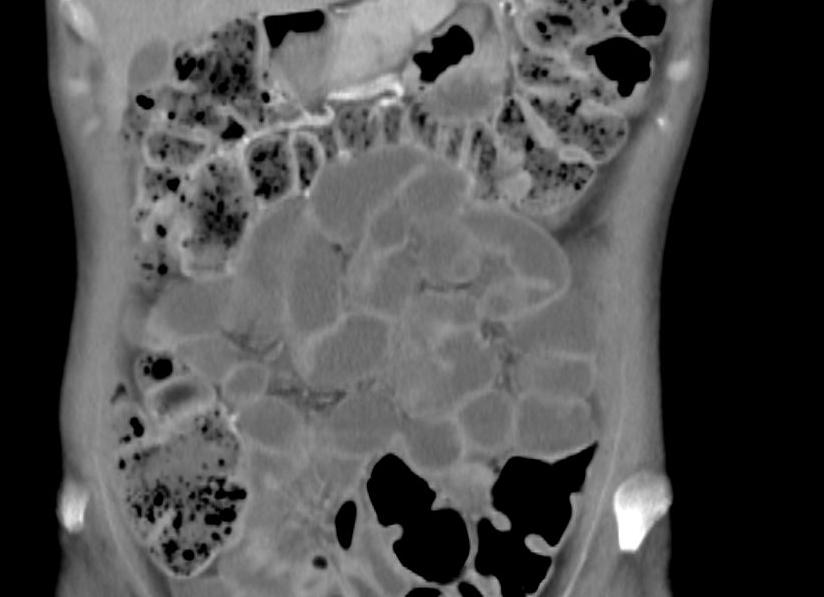

В последнее десятилетие наряду с классическими рентгенологическими методами для изучения состояния кишечника при таких заболеваниях как аппендицит, болезнь Крона (терминальный илеит), непроходимость кишечника активно внедряется ультразвуковое исследование. В связи с внедрением в широкую клиническую практику спиральных томографов и возможности получения изображения за короткий промежуток времени с минимальной лучевой нагрузкой, КТ становится скрининговым методом в диагностике колоректального рака. Кроме того, спиральная КТ эффективна в диагностике кишечной непроходимости и дивертикулита.

Рентгенологическое исследование выполняется прежде всего у пациентов с подозрением на опухоль кишечника и кишечную непроходимость для решения вопроса о причине нарушения пассажа кишечного содержимого (механическая или динамическая непроходимость) и уточнения локализации патологического процесса (тонкокишечная или толстокишечная непроходимость).

Для исключения тонкокишечной непроходимости больному достаточно выпить 100 мл бариевой взвеси, контрольные исследования выполняются в зависимости от клинической картины через 1,5-2 – 4 часа до перехода бария через илеоцекальный угол в толстую кишку.